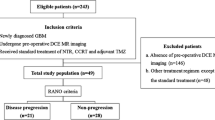

This study was approved by the institutional review board (IRB), which waived informed consent. A total of seventy-three AA patients who had undergone preoperative DCE and DSC MRI and received standard treatment, including partial resection or biopsy followed by radiation therapy, were included in this retrospective study. Based on Response Assessment in Neuro-Oncology (RANO), patients were sorted into progression (n = 21) and non-progression (n = 52) groups. Tumor boundaries were defined as high-signal intensity (SI) lesions on fluid-attenuated inversion recovery (FLAIR) imaging, where we analyzed mean pharmacokinetic parameters (Ktrans, Vp, and Ve) from DCE MRI and contrast leakage information (mean extraction fraction (EF)) from DSC MRI.